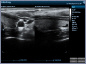

Neben einem ausführlichen Gespräch, der Anamnese, Zeit und Zuwendung gehören auch die Anwendung von wissenschaftlich evaulierten diagnostischen Verfahren zu einer guten Eingangsuntersuchung. Ich freue mich Ihnen in meiner Praxis deshalb nun auch die Ultraschalluntersuchung mit modernster Technik, einem mindray Consona N6 anbieten zu können.

- Darstellung der Schilddrüse - Darstellung der hirnversorgenden Gefäße mit Messung der Intimadicke (IMD) - Ultraschall des Herzens z. B. Stenose / Dichtigkeit der Herzklappen, Wandbewegungsstörungen,... - Ultraschall des Bauchraumes wie Leber, Gallenblase, Nieren, Blase, Milz. - Gefäßdarstellung

Video Farbdoppler der Halsarterie zur Darstellung der Durchblutung Video Farbdoppler der Niere zur Darstellung der Durchblutung Video Herzultraschall eines gesundes Herzens mit guter Pumpfunktion Video Herzultraschall mit eingeschränkter Pumpfunktion und vergrößerten Vorhöfen Video Herzultraschall bei Herzinsuffizienz und undichter Herzklappe